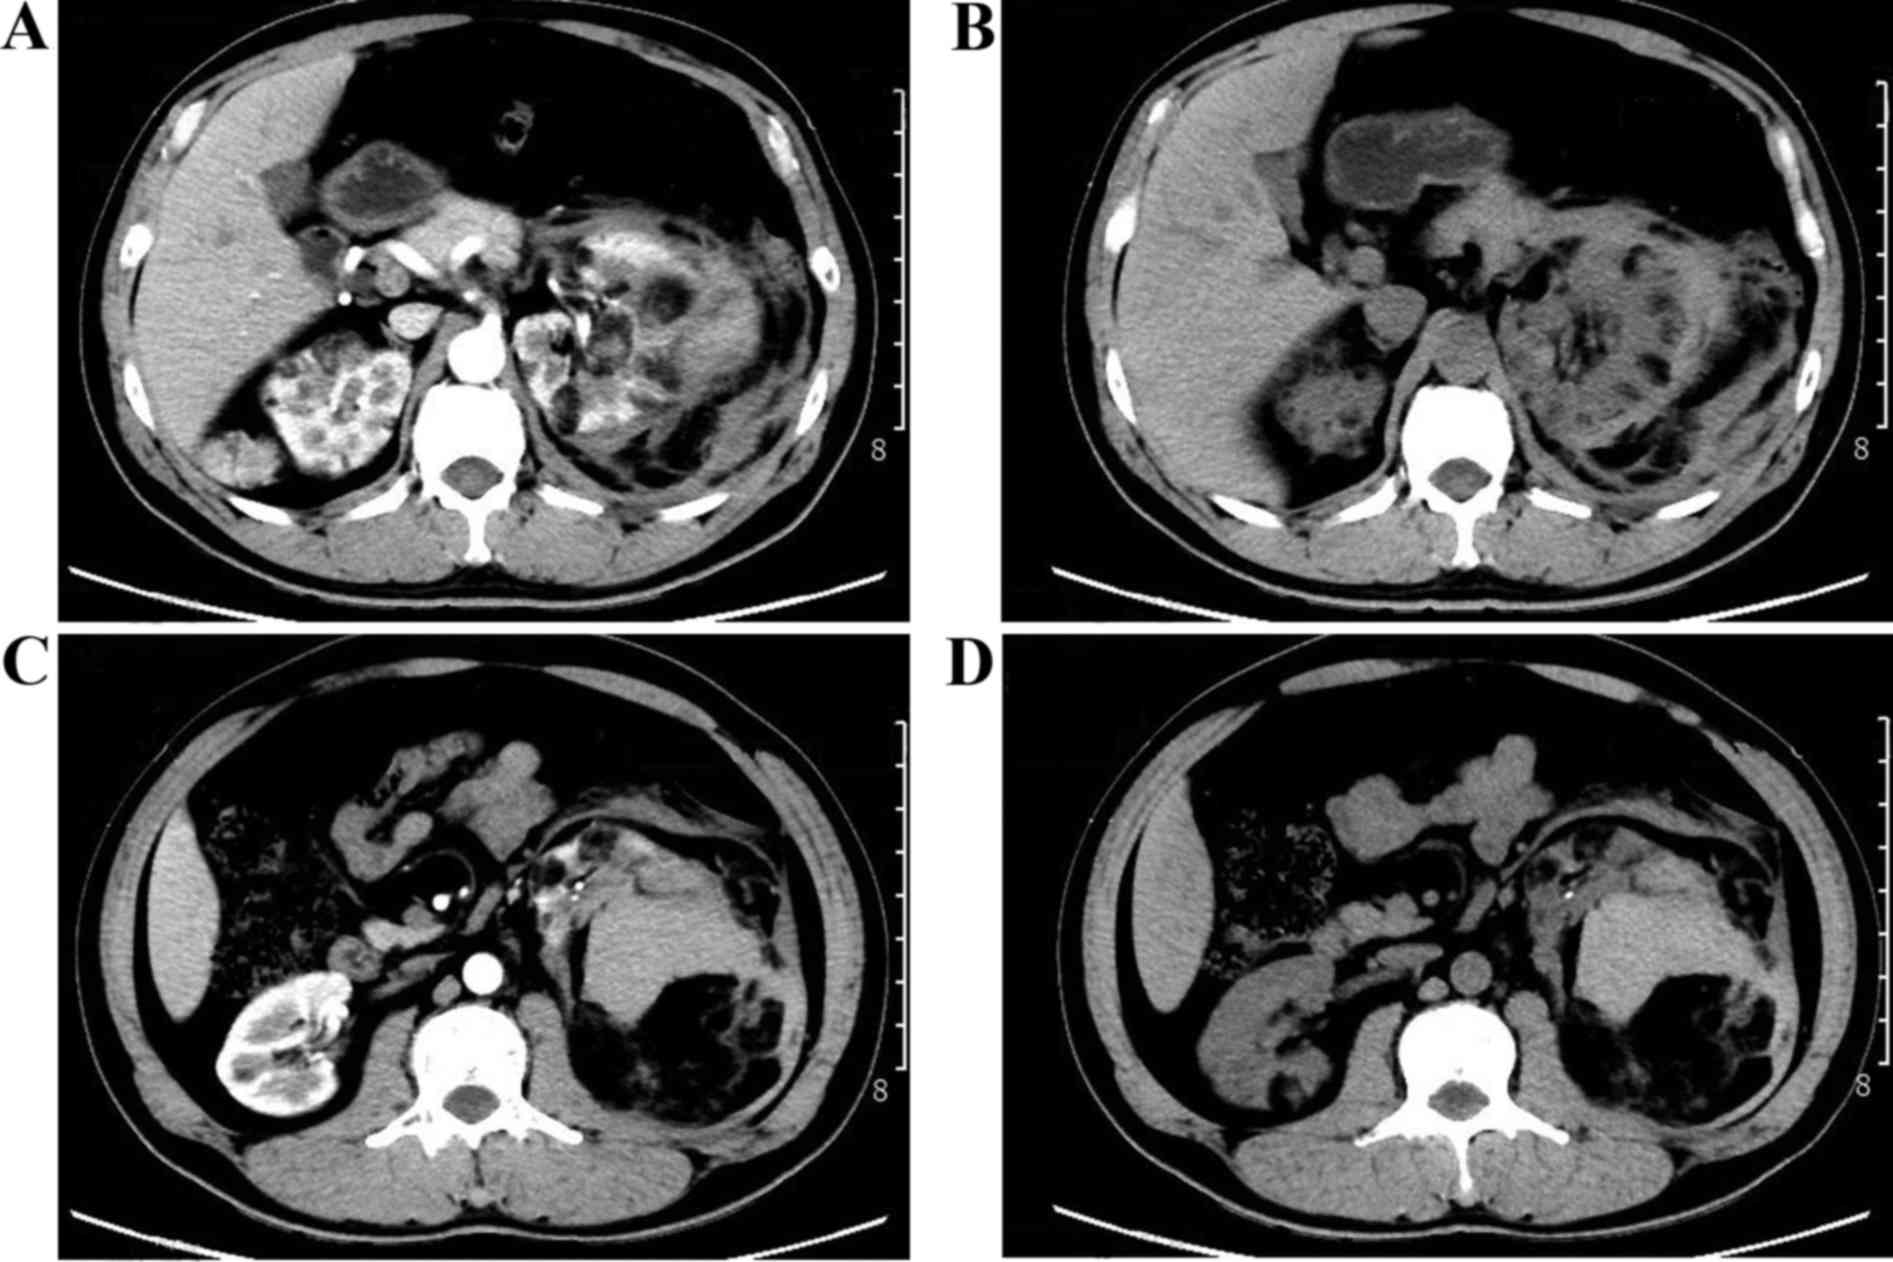

Tuberous sclerosis-associated renal angiomyolipoma: A report of two cases and review of the literature

In the general population, tuberous sclerosis‑associated renal angiomyolipoma (RAML) is a rare benign hamartoma with potentially life‑threatening complications and a poor prognosis. The two patients reported in the present study, who were diagnosed with bilateral RAML and spontaneous rupture of the RAML with tuberous sclerosis, presented with flank pain, abdominal pain, hemorrhage, hematuria and multiple lesions. The two cases are representative examples of the disease, and highlight the importance of determining the risk of acute hemorrhage in the early stages, and the significance of timely and proper treatment.

Figure 1

Figure 2

Figure 3

Figure 4

Figure 5